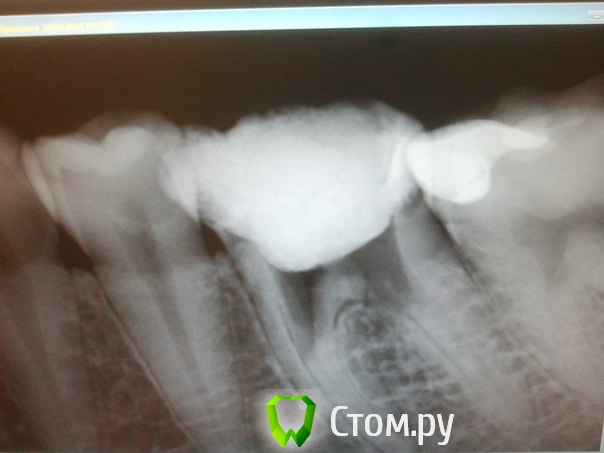

Инна Владимировна Опубликовано 25 июня, 2014 Автор Поделиться Опубликовано 25 июня, 2014 Все, товарищи, сходила. Зуб оказался как решето. Но все равно решили помучиться - залепили, залили... Врачи очень старались))) Прошло вот 5 часов, болит, конечно. И все удивились, зачем первый врач -Елонова Елена Анатольевна так издырявила зуб. Ссылка на комментарий

DokDent Опубликовано 25 июня, 2014 Поделиться Опубликовано 25 июня, 2014 Все, товарищи, сходила. Зуб оказался как решето. Но все равно решили помучиться - залепили, залили... Врачи очень старались))) Прошло вот 5 часов, болит, конечно. И все удивились, зачем первый врач -Елонова Елена Анатольевна так издырявила зуб. А снимок? Интересно глянуть 1 Ссылка на комментарий